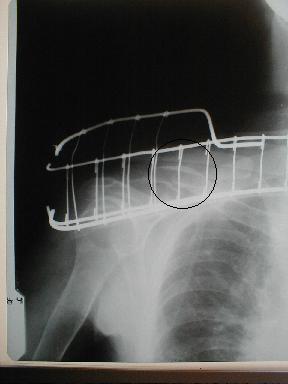

10月28日整復固定x-p

整復固定は、症例2を参照